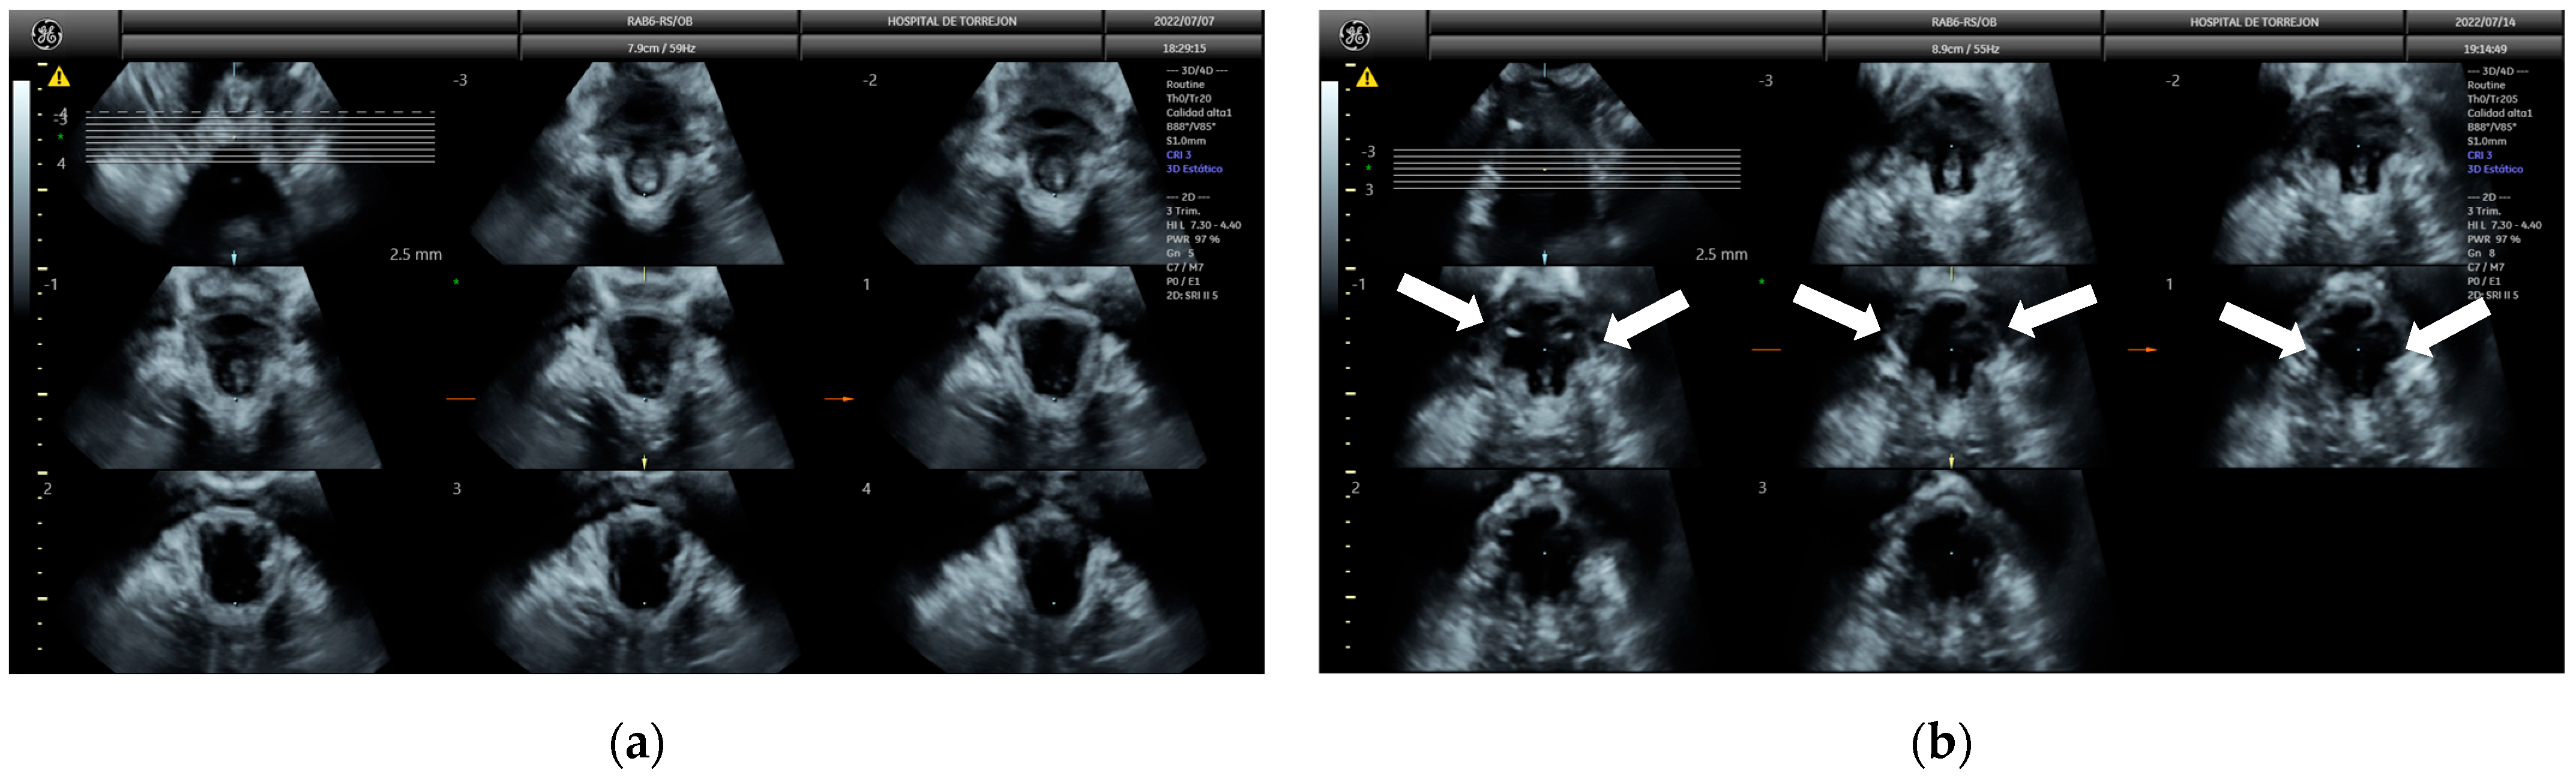

2.6. Pelvic Floor Ultrasound

- Dietz, H.P. Ultrasound imaging of the pelvic floor. Part II: Three-dimensional or volume imaging. Ultrasound Obstet. Gynecol. 2004, 23, 615–625. [Google Scholar] [CrossRef] [PubMed]

- Volløyhaug, I.; Mørkved, S.; Salvesen, Ø.; Salvesen, K.Å. Assessment of pelvic floor muscle contraction with palpation, perineometry and transperineal ultrasound: A cross-sectional study. Ultrasound Obstet. Gynecol. 2016, 47, 768–773. [Google Scholar] [CrossRef] [PubMed]